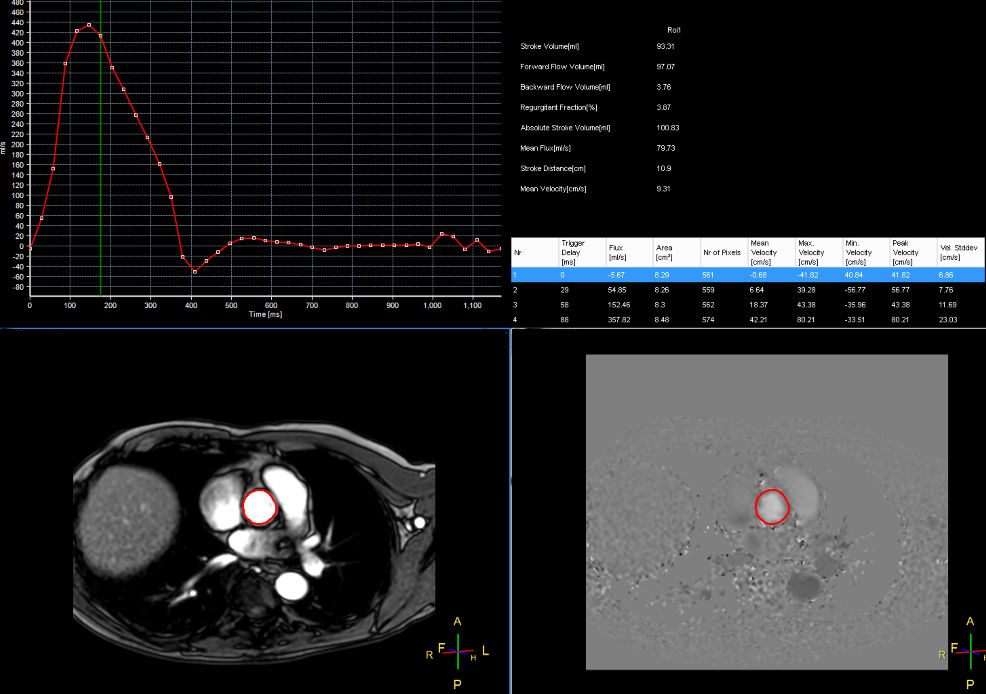

Qflow aorta